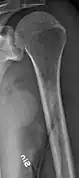

-

X-ray of the forearm, with lytic lesions -

Multiple myeloma in the upper arm -

Humerus with multiple myeloma lesions -

Same humerus before, with just subtle lesions